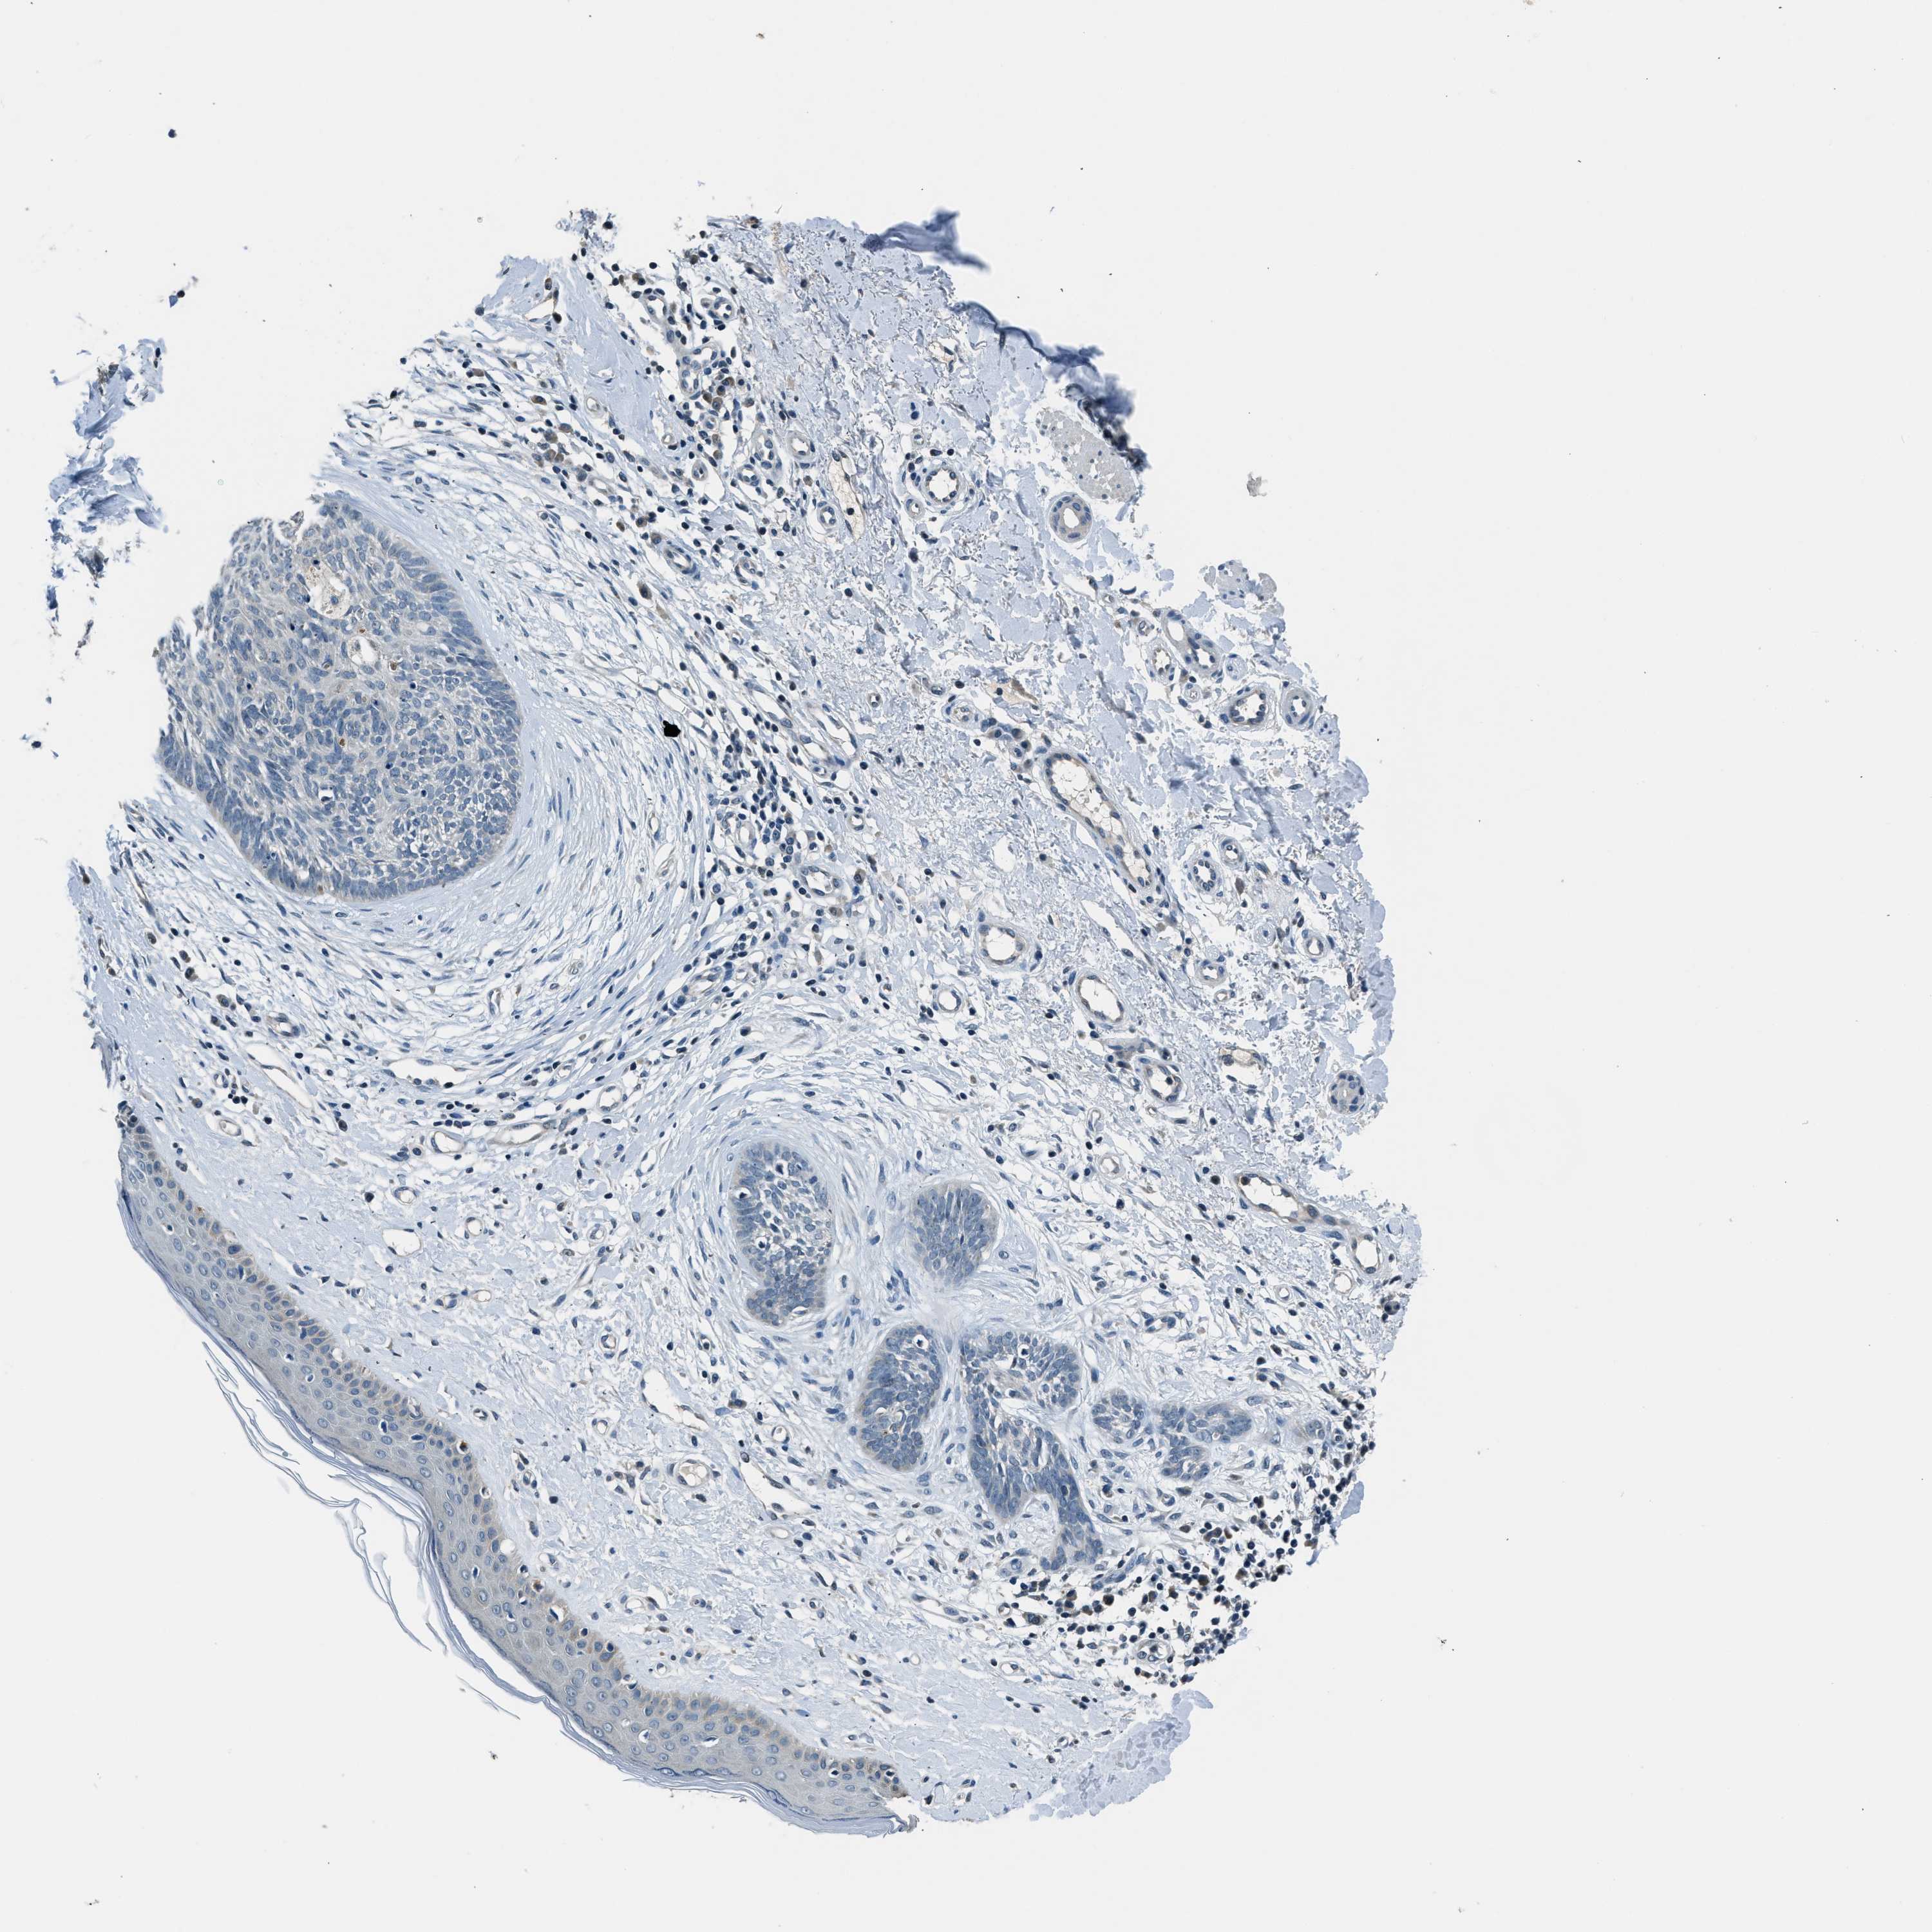

SKIN CANCER - Protein expressioni

A mouse-over function shows sample information and annotation data. Click on an image to view it in a full screen mode. Samples can be filtered based on level of antibody staining by selecting one or several of the following categories: high, medium, low and not detected. The assay and annotation is described here.

Antibody stainingi

Antibody staining in the annotated cell types in the current human tissue is reported as not detected, low, medium, or high, based on conventional immunohistochemistry profiling in selected tissues. This score is based on the combination of the staining intensity and fraction of stained cells.

Each image is clickable and will lead to virtual microscopy that enables deeper exploration of all samples and also displays staining intensity scores, fraction scores and subcellular localization as well as patient and tissue information for each sample.

Antibody CAB016416

Squamous cell carcinoma, NOS